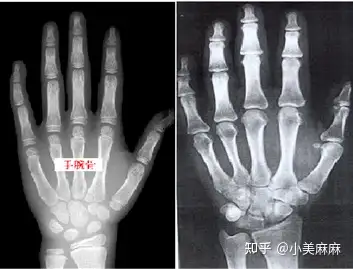

骨骼年龄简称骨龄,是由儿童的骨骼钙化程度所决定的.

骨骺线结果出来了,双腕部诸骨均出现,双侧桡骨及尺骨远端干骺端规则

帮忙看下骨骺线是否闭合还能长多高谢谢